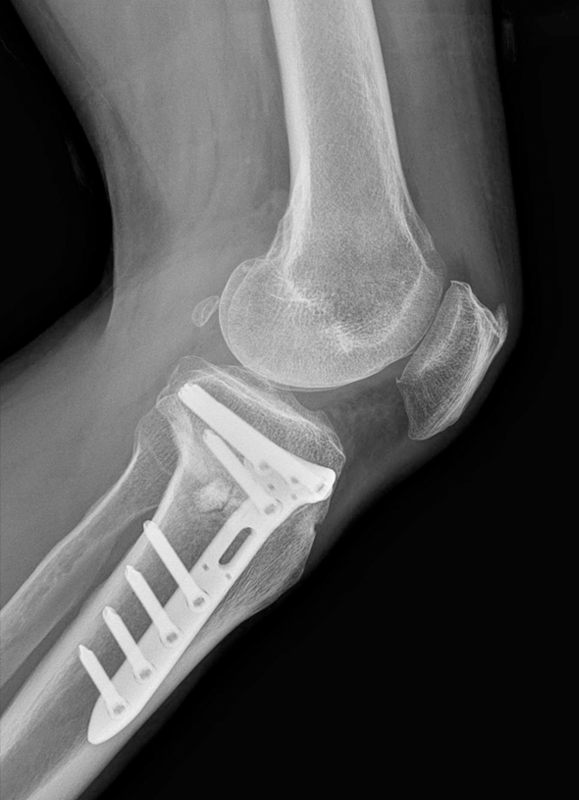

무릎절골술은 인공관절처럼

관절을 제거하거나 바꾸는 수술이 아닙니다.

체중이 한쪽으로 쏠려

'특정 부위 연골'만 빠르게 닳고 있을 때,

뼈의 각도를 미세하게 교정해 체중이 실리는 축을 다시 균등하게 나누는 수술입니다.